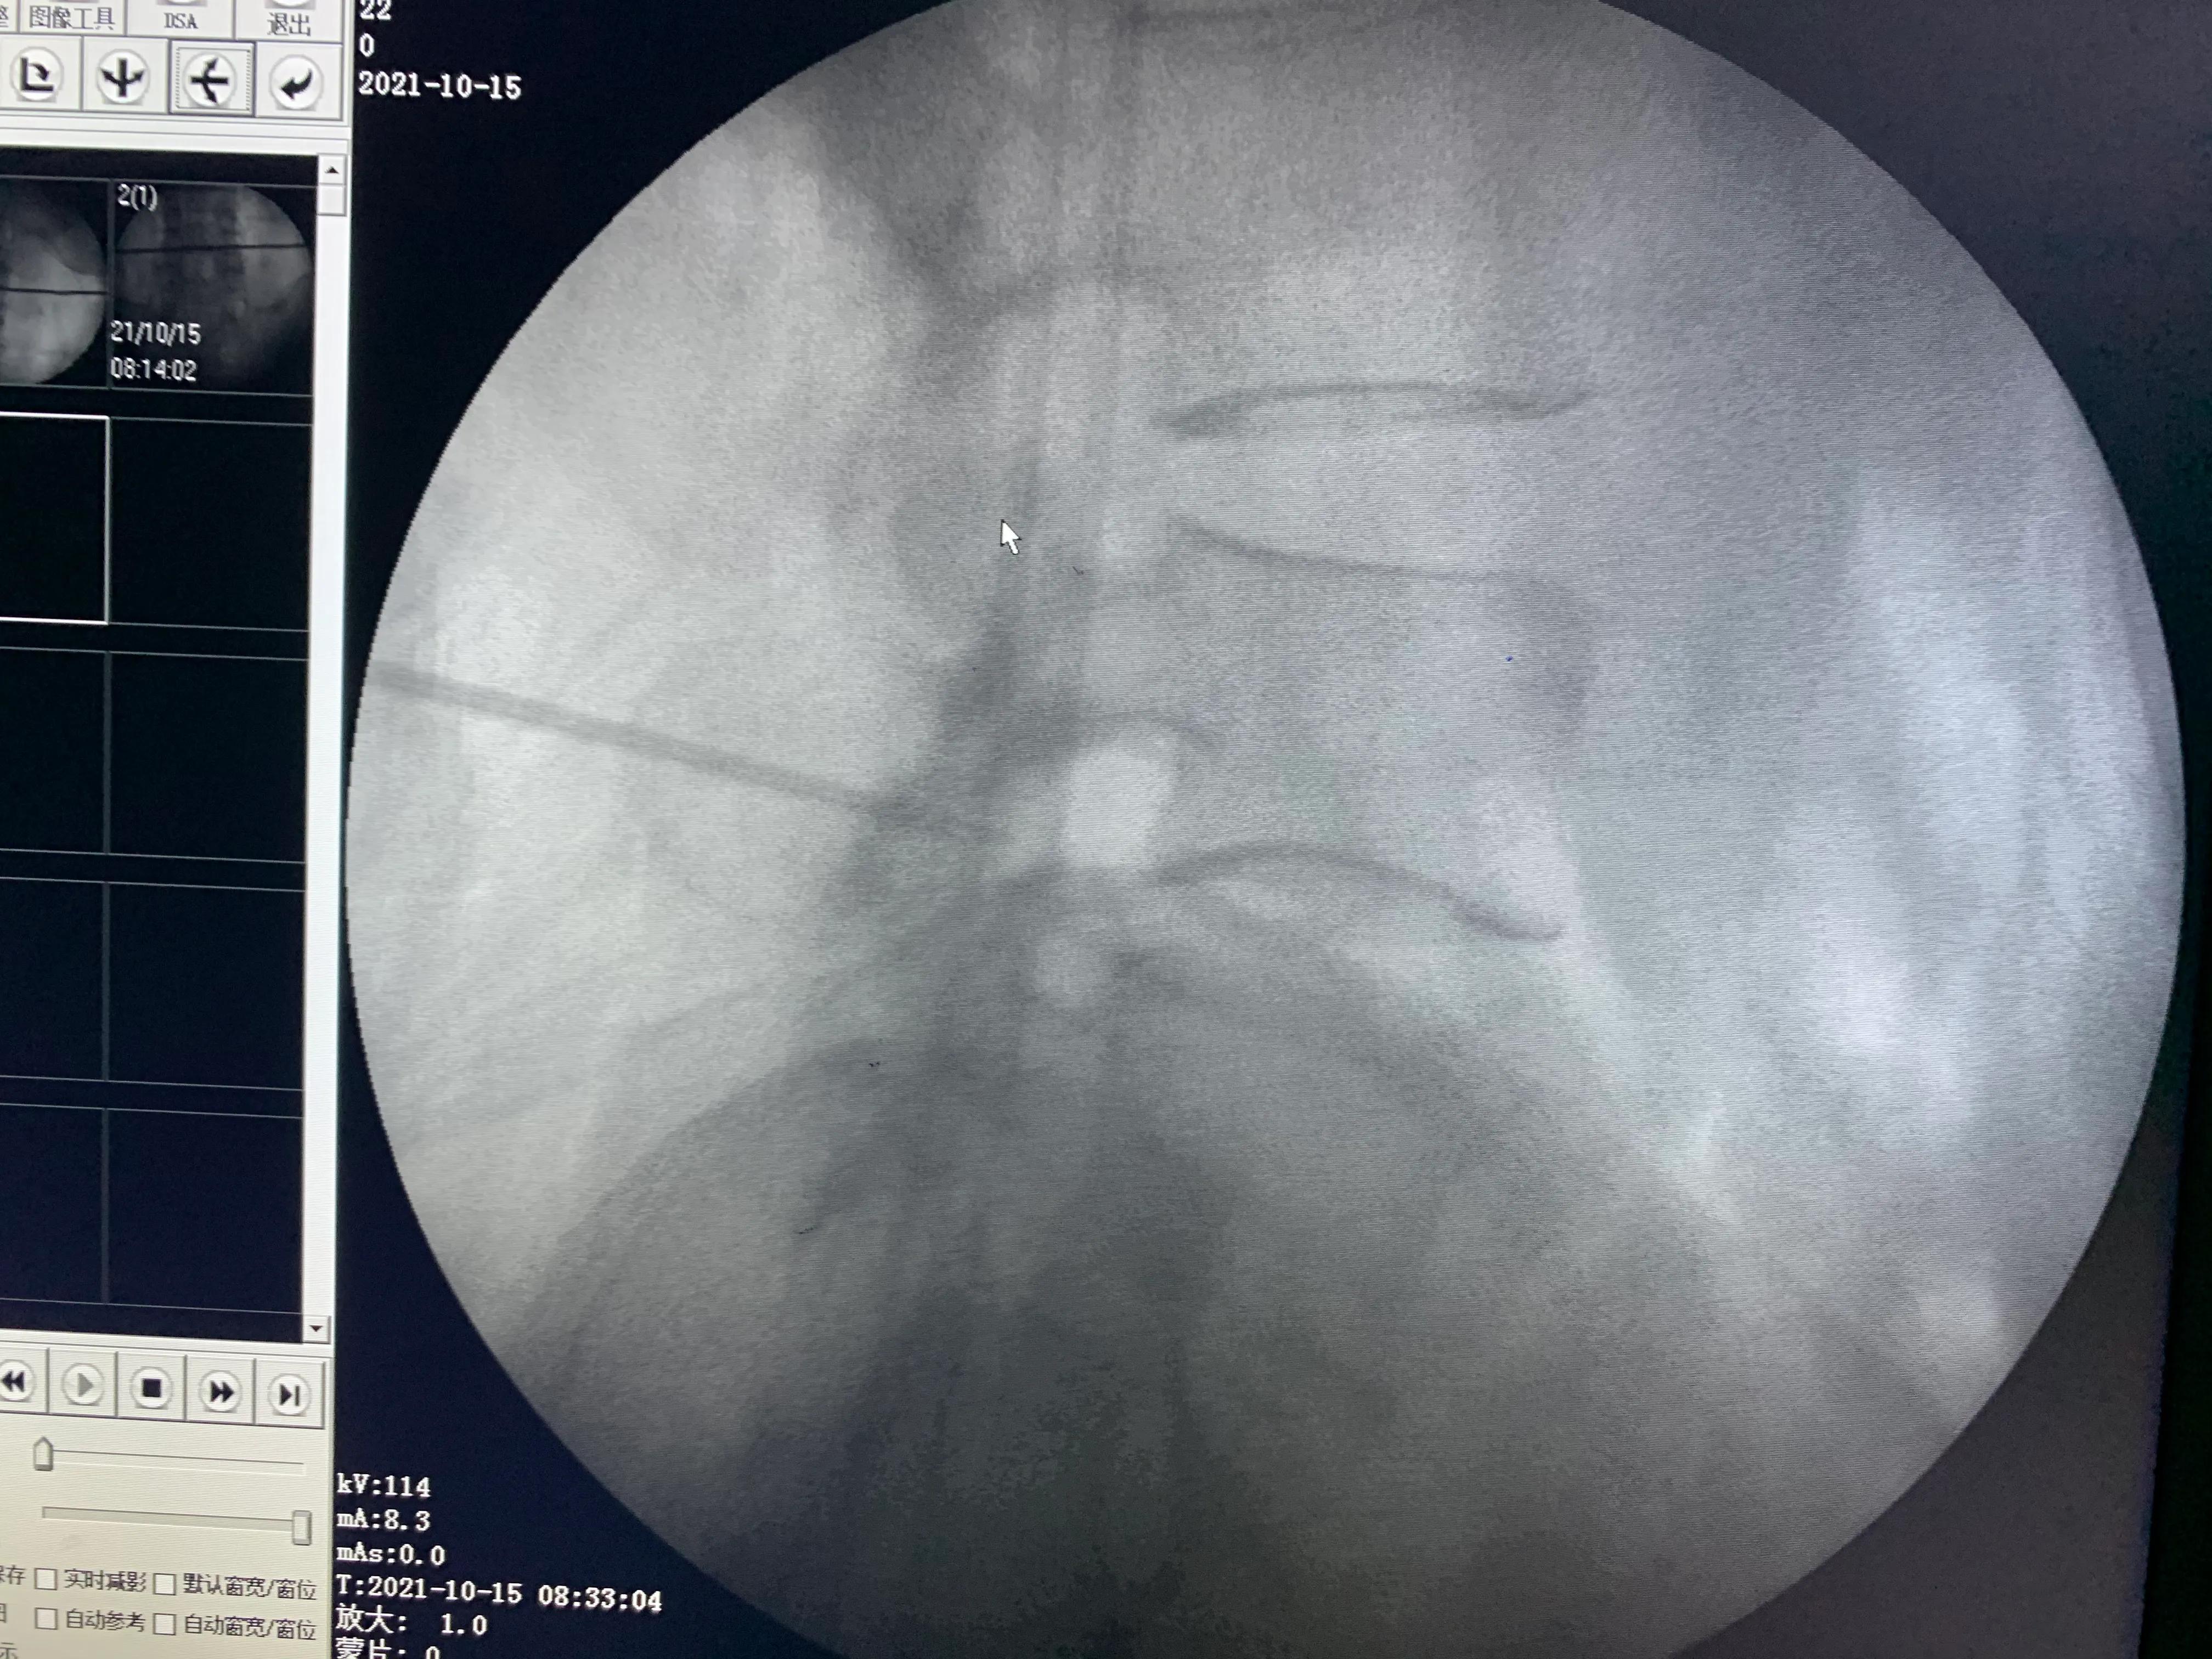

术中定位不清,一定要透视,不要盲目开口

术中透视